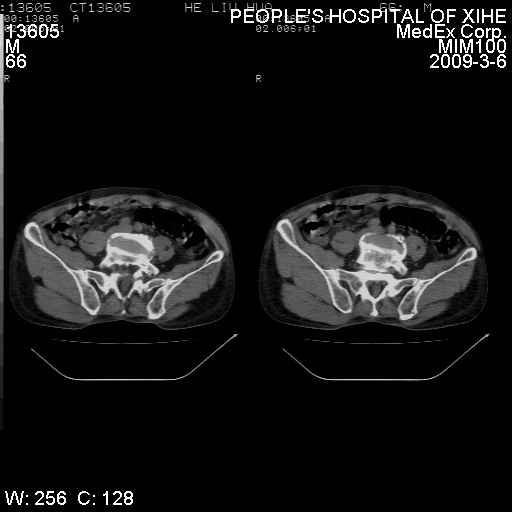

考虑----腰椎骶化-----退变-----椎管狭窄

腰骶椎退行性改变。

腰骶椎退行性改变,建议重建看看!

退行性变,椎体滑脱

腰椎滑脱并有退变

资料不清,考虑退变

退行性变,椎体滑脱。建议同椎体平行进一步扫描。